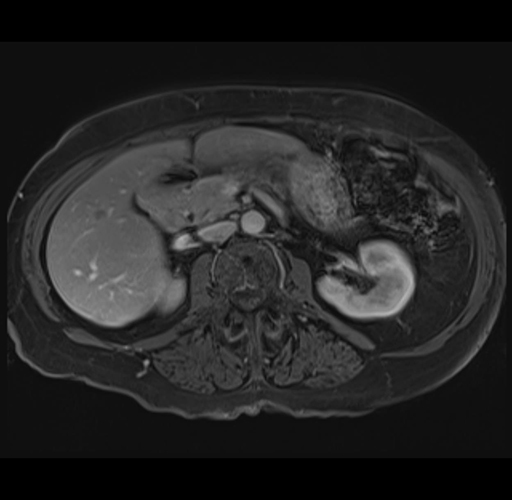

MRI T1

Imaging analysis

Based on your CT findings, which issue(s) would give reason for "planned slowing down moment(s)" in this case?

Considering a standard right hepatectomy procedure, what step(s) of the operation would you do differently in this case?